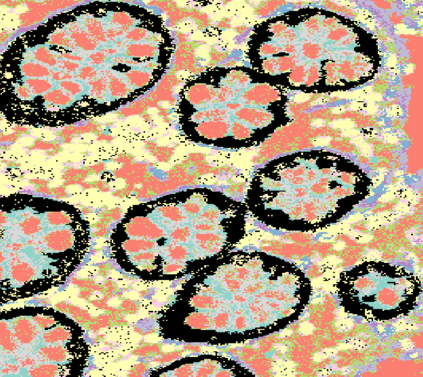

The usage of chemical imaging technologies is becoming a routine accompaniment to traditional methods in pathology. Significant technological advances have developed these next generation techniques to provide rich, spatially resolved, multidimensional chemical images. The rise of digital pathology has significantly enhanced the synergy of these imaging modalities with optical microscopy and immunohistochemistry, enhancing our understanding of the biological mechanisms and progression of diseases. Techniques such as imaging mass cytometry provide labelled multidimensional (multiplex) images of specific components used in conjunction with digital pathology techniques. These powerful techniques generate a wealth of high dimensional data that create significant challenges in data analysis. Unsupervised methods such as clustering are an attractive way to analyse these data, however, they require the selection of parameters such as the number of clusters. Here we propose a methodology to estimate the number of clusters in an automatic data-driven manner using a deep sparse autoencoder to embed the data into a lower dimensional space. We compute the density of regions in the embedded space, the majority of which are empty, enabling the high density regions to be detected as outliers and provide an estimate for the number of clusters. This framework provides a fully unsupervised and data-driven method to analyse multidimensional data. In this work we demonstrate our method using 45 multiplex imaging mass cytometry datasets. Moreover, our model is trained using only one of the datasets and the learned embedding is applied to the remaining 44 images providing an efficient process for data analysis. Finally, we demonstrate the high computational efficiency of our method which is two orders of magnitude faster than estimating via computing the sum squared distances as a function of cluster number.